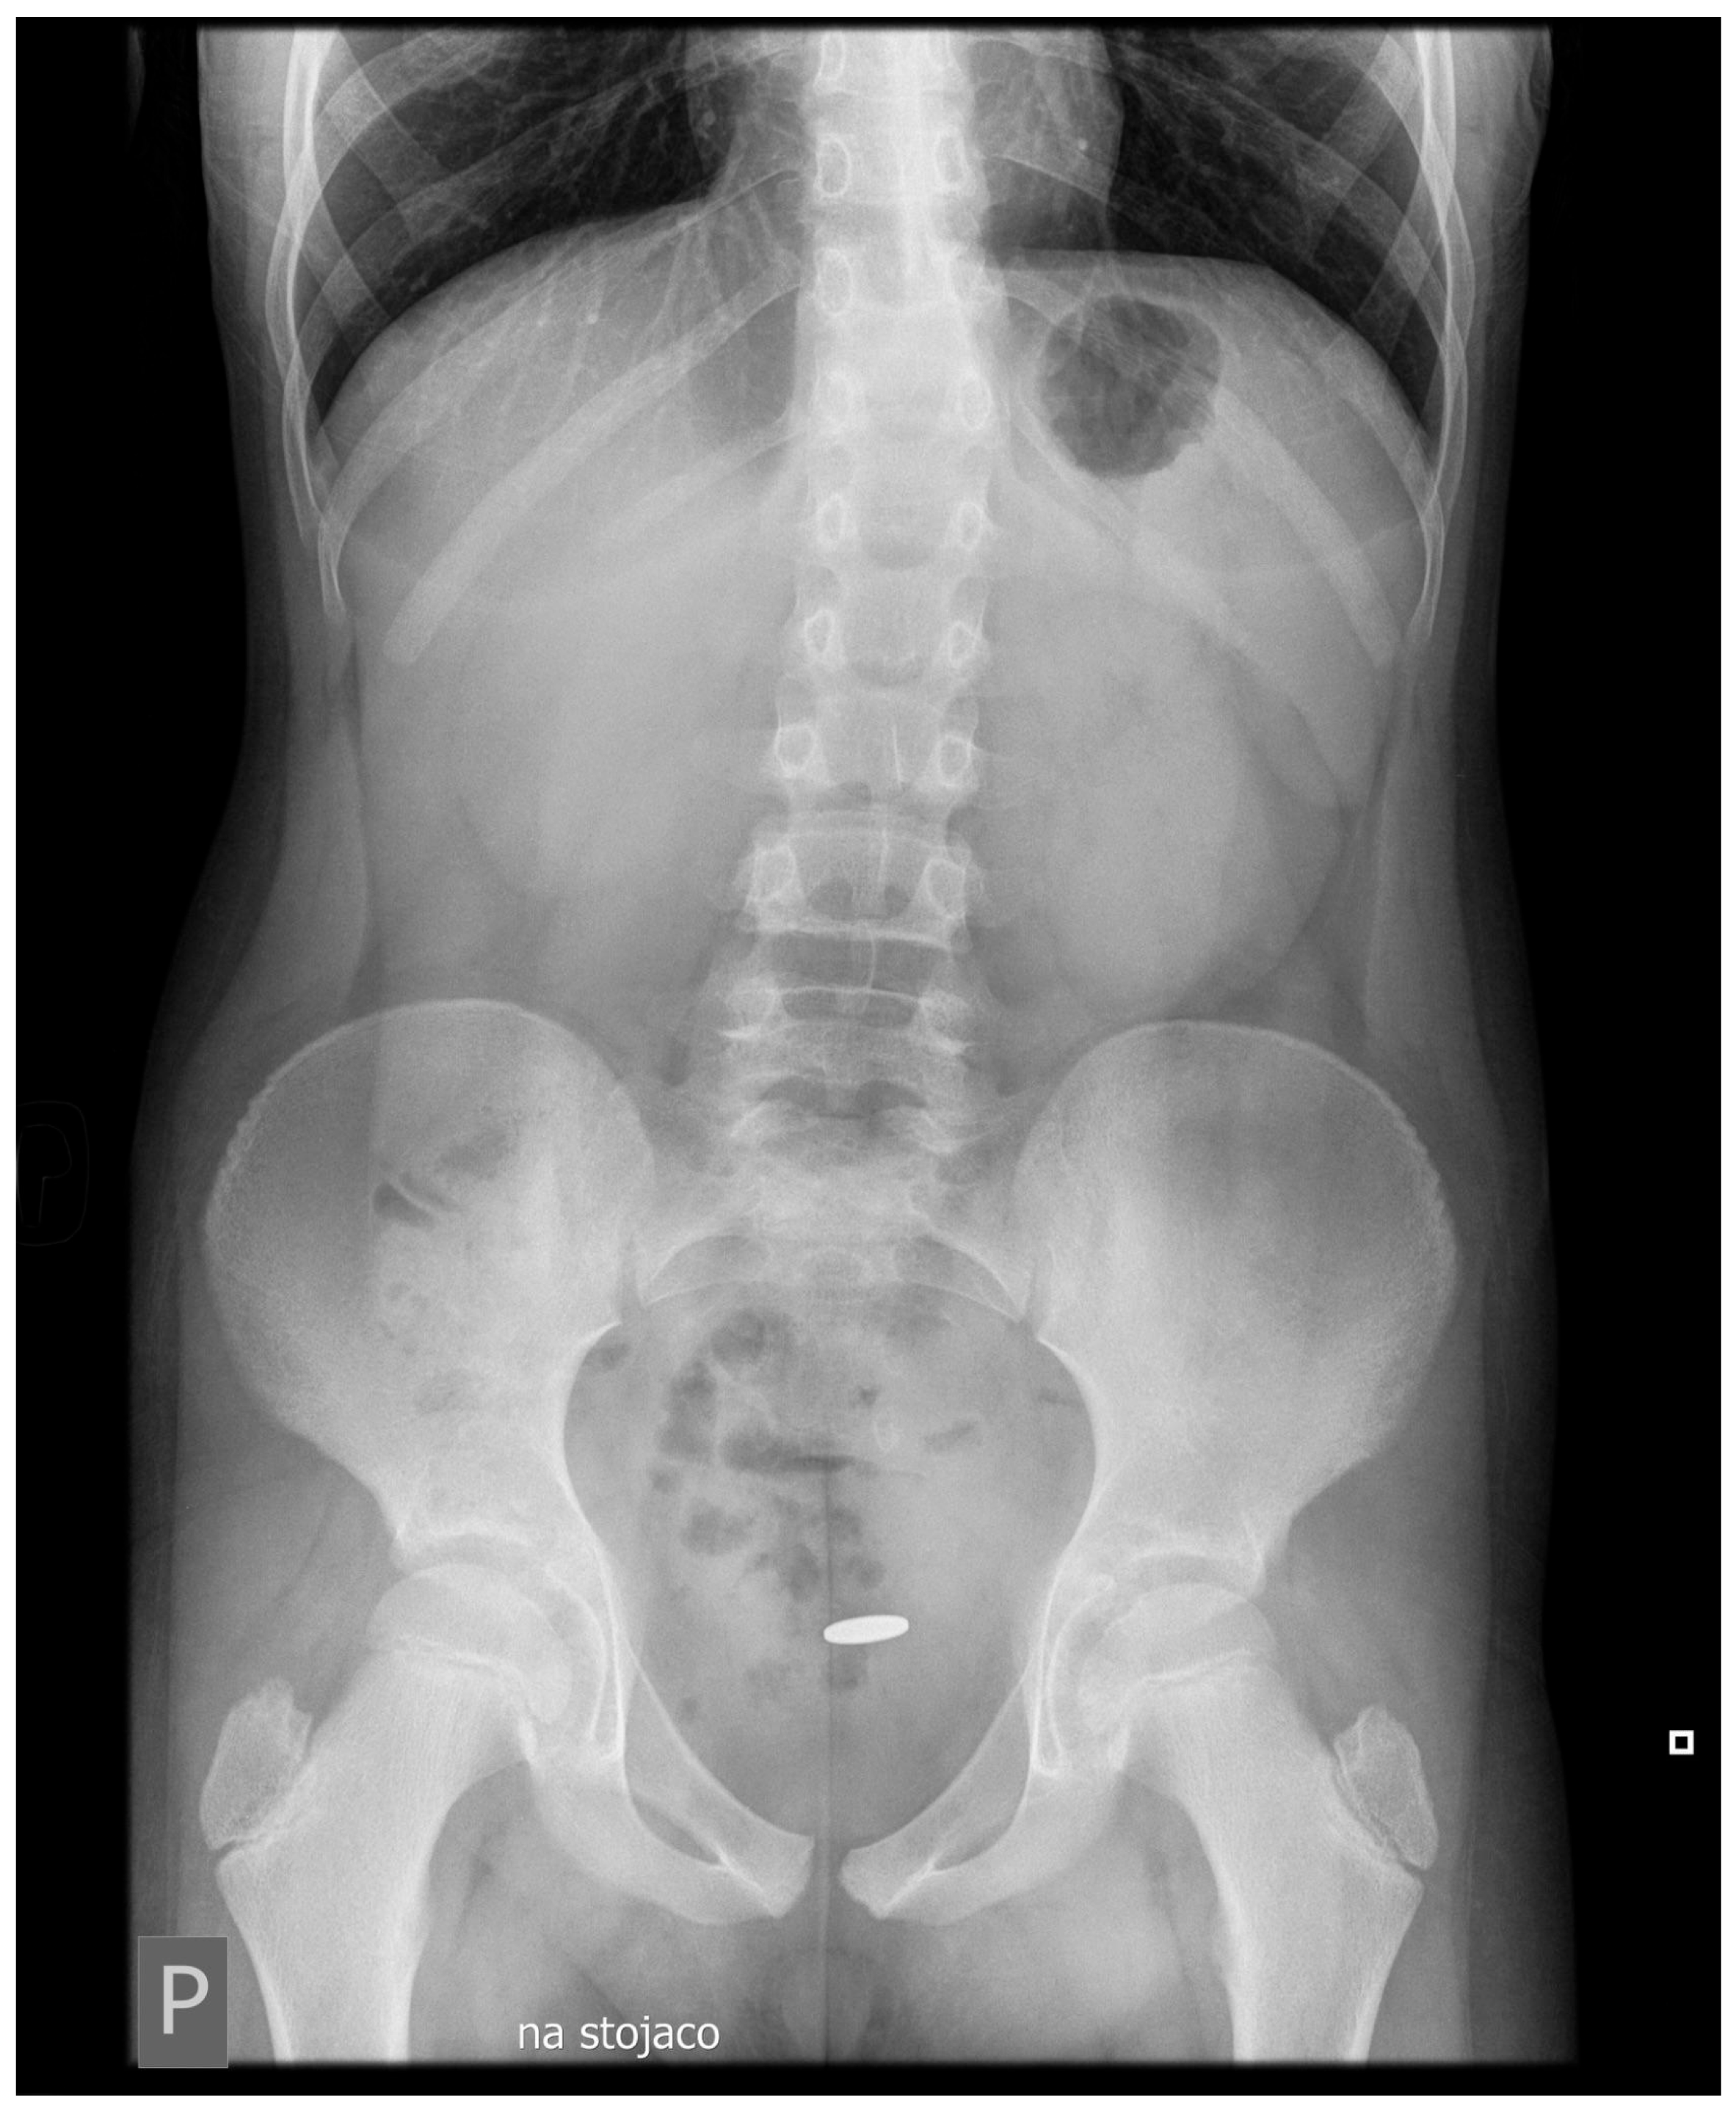

1.1. Case Presentation

1.2. Investigations